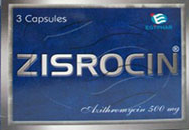

zisrocin زيثروسين برشامة كل 24 ساعة لمدة 3 ايام

zisrocin زيثروسين برشامة كل 24 ساعة لمدة 3 ايام